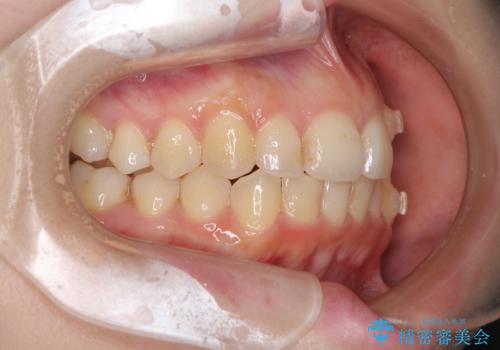

顕著な八重歯をインビザラインで治せるところまで改善

- 顕著な八重歯など、上下前歯のデコボコとスペースを気にして来院された患者様です。

八重歯改善には第一小臼歯の抜歯が必要であり、移動量が多いことから補助装置により八重歯を引き込むこととしました。

インビザラインでの治療をご希望であったので、インビザラインにて行うこととしましたが、右側前歯の改善にはワイヤー矯正が必要となる可能性があることをお伝えした上で治療を開始しました。

補助装置だけでなく、部分的にワイヤー矯正も使用しましたが、上下のスペースは改善しきれず、側切歯(前から2番目の歯)や顕著な八重歯は、インビザラインで治療するには限界があることがよく分かりました。

より良い仕上がりを希望される場合には、ワイヤー装置による矯正治療がお勧めとなります。